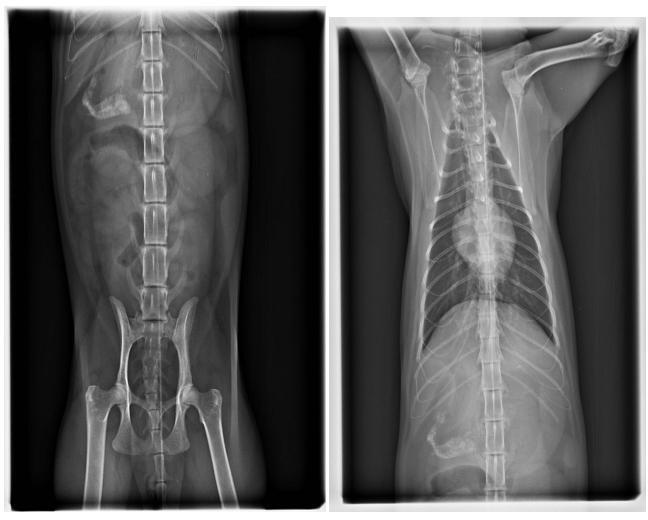

經檢查發現,

貓咪疑似受到撞擊.雙眼縮瞳.神經反應差.有神經症狀

呼吸急促.鼻腔出血

2.X-RAY 400*6